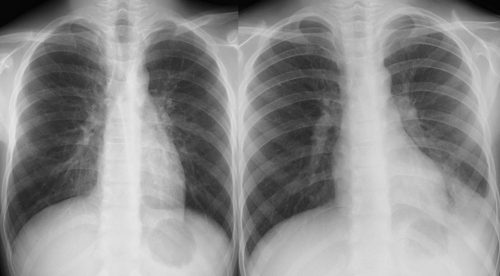

[区域性分布と非区域性分布の理解] ***下図を参考に大葉性・小葉性と区域性・非区域性を混同しないこと。 [マイコプラズマ肺炎陰影の成り立ち] [参考1]マイコプラズマ肺炎の2型 [参考2]マイコプラズマ肺炎の2型 [参考3]マイコプラズマ肺炎(肺胞性間質性)

右肺下肺野では肺胞性陰影(浸潤影・airbronchogram)と間質性陰影(水平裂外側の下方への偏移・tram line・線状影等)が混在している。 [参考]右肺は均等影様にみえるが左肺と同じ透過性不良のすりガラス様陰影で間質性の陰影。 [びまん性肺病変の基本型] びまん性肺疾患 間質性陰影と肺胞性陰影